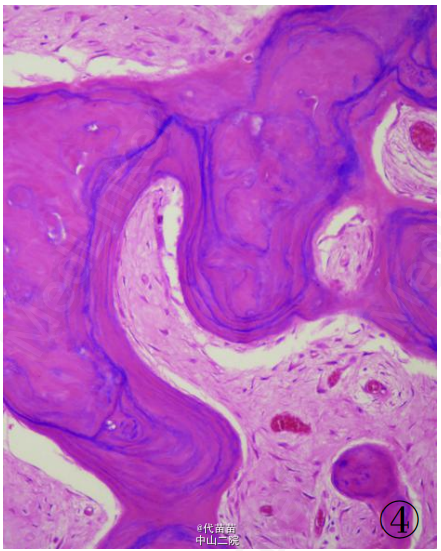

患者男性,40 岁。因体检发现肋骨肿块入院。患者无其它特殊症状,血生化检查基本正常,无放、 化疗史及Paget病史。CT检查示右侧第九后肋骨旁一团块状混杂高密度影,肿块边界尚清,位于肋骨表面,非髓内生长,向胸腔隆起,位于壁层胸膜与肋骨之间,与骨皮质有蒂相连(图 1、2)。临床考虑良性病变骨软骨瘤可能,遂行手术切除一段肋骨及表面肿块,送病理检查。 病理检查:眼观:送检肋骨1段,长9cm,宽2cm,骨表面隆起卵圆形肿块,4 cmX2 cmX2 cm 大小,质硬,切面灰白色,实性,与骨皮质有蒂相连,蒂部骨皮质浸润(图 3)。镜检:肿瘤由大量狭长且具平行排列倾向的高分化骨小梁构成,以编织骨为主,部分骨小梁已成熟为板层骨,大部分骨小梁周围缺乏成骨细胞被覆,部分区域已逐渐移行为有成骨细胞被覆的板层骨,瘤骨内可见骨重建过程中形成的粘合线,即所谓“Paget” 现象(图 4)。骨小梁间充满低细胞性纤维组织间质,梭形成纤维细胞形态温和,细胞核卵圆形,缺乏不典型性,部分肿瘤性骨小梁之间有脂肪髓形成,但无造血组织。肿瘤表面的骨样组织较幼稚,深部为相对成熟的粗大编织骨和板层骨(图 5),蒂部皮质和近皮质的髓腔内有局灶性肿瘤浸润(图 6)。肿瘤内含多灶性高分化软骨,软骨细胞排列紊 乱无极性,由于部分软骨位于肿瘤表面,故影像学和病理学类似骨软骨瘤改变。病理诊断:右侧第九后肋骨旁骨肉瘤。 骨旁骨肉瘤临床表现为骨表面缓慢生长的无痛性肿块,质硬,病程较长,可达数年。骨旁骨肉瘤预后较好,其5 年生存率达91% ,最佳治疗方案是大块肿瘤完整切除,切除范围应包括肿瘤周围的正常组织和软组织内的卫星病灶。若不完整切除则很容易复发。复发性肿瘤易发生去分化改变,称去分化骨旁骨肉瘤,其预后类普通型骨肉瘤,治疗原则和普通高级别骨肉瘤一致。 骨旁骨肉瘤可以说是骨肉瘤中的“异类” ,因为其不仅分化好,类似良性骨病,而且在骨表面生长,在病理诊断时须注意与以下三种良性骨病鉴别:(1)纤维结构不良。本例虽然部分肿瘤性编织骨呈不连续的字母状结构,在编织骨之间为高分化纤维,类似于纤维结构不良,但纤维结构不良是一 种纤维化生骨,伴有骨的成熟障碍,不会成熟为板层骨,也不会出现板层结构瘤骨在改建塑型过程中形成“Paget”现象。本例镜下见瘤骨比较成熟、 粗大,大部分相互连接成网,并有平行排列倾向,肿瘤表面骨样组织幼稚,深部较为成熟,并形成板层骨,成熟瘤骨内能见到“ 孕葬早藻贼” 现象。此外纤维结构不良均在髓内生长,不会在骨表面外生性生长,故影像学改变即可排除纤维结构不良。(2)骨软骨瘤。本例肿瘤内含有少量高分化软骨组织,由于部分软骨位于肿瘤表面,需与骨软骨瘤鉴别。骨软骨瘤蒂部的骨皮质常有缺损,肿瘤内的松质骨与宿主骨的正常松质骨相连续,二者相互融合。而骨旁骨肉瘤常环绕宿主骨在骨膜外生长,与髓腔不相通,肿瘤与骨密质之间有狭长的透亮带,即残存的骨膜;骨软骨瘤软骨帽下是由软骨化骨形成的松质骨小梁,骨小梁间隙内充满正常的造血性红髓或脂肪性黄髓,而缺乏骨旁骨肉瘤的成纤维细胞成分。同时骨旁骨肉瘤内的软骨组织、 结构和分布随意紊乱,缺乏骨软骨瘤明显的分层结构。(3)骨旁骨瘤。大多位于颅骨表面或副鼻窦内,分化成熟的骨小梁之间为脂肪细胞和小血管,缺乏纤维母细胞性间质。